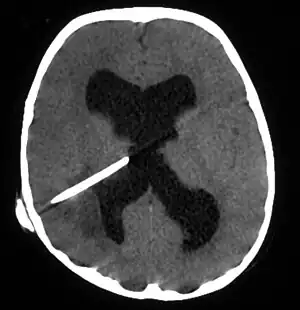

The diagnosis is established by a computed tomography (CT) (with contrast) examination. At the initial phase of the inflammation (which is referred to as cerebritis), the immature lesion does not have a capsule and it may be difficult to distinguish it from other space-occupying lesions or infarcts of the brain. Within 4–5 days the inflammation and the concomitant dead brain tissue are surrounded with a capsule, which gives the lesion the famous ring-enhancing lesion appearance on CT examination with contrast (since intravenously applied contrast material can not pass through the capsule, it is collected around the lesion and looks as a ring surrounding the relatively dark lesion). Lumbar puncture procedure, which is performed in many infectious disorders of the central nervous system is contraindicated in this condition (as it is in all space-occupying lesions of the brain) because removing a certain portion of the cerebrospinal fluid may alter the concrete intracranial pressure balances and causes the brain tissue to move across structures within the skull (brain herniation).

CT guided stereotactic aspiration is also indicated in the treatment of brain abscess. The use of pre-operative imaging, intervention with post-operative clinical and biochemical monitoring used to manage brain abscesses today dates back to the Pennybacker system pioneered by Somerset, Kentucky-born neurosurgeon Joseph Buford Pennybacker, director of the neurosurgery department of the Radcliffe Infirmary, Oxford from 1952 to 1971. [12]